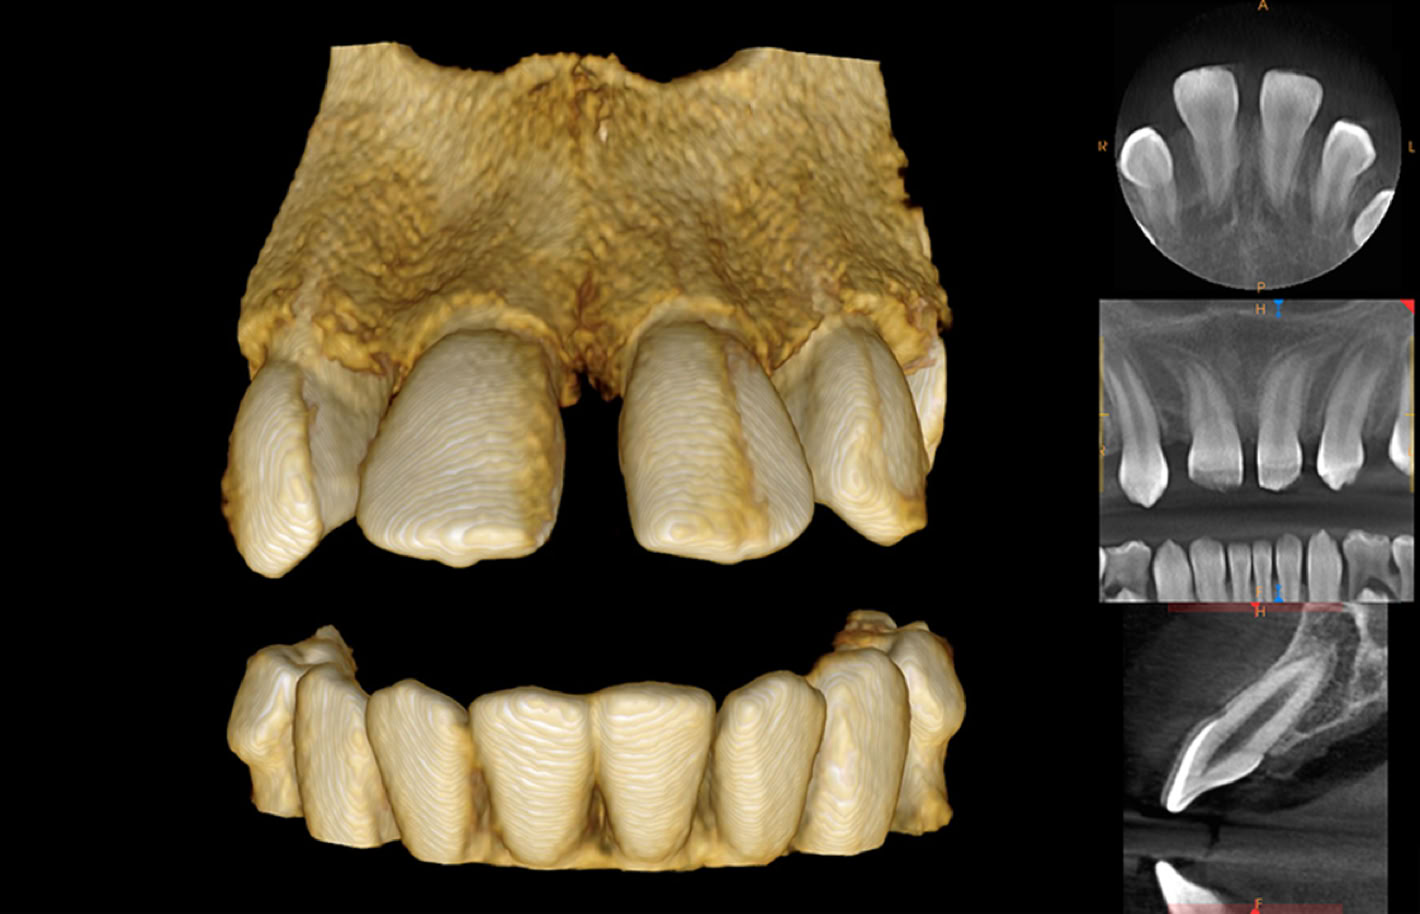

Wir finden die richtige Einstellung zur Beantwortung Ihrer Fragen.

FIELD OF VIEW

BIS ZU EINER GRÖSSE VON 17 cm x 13,5 cm

Mit der derzeit modernsten und strahlungsarmsten digitalen Aufnahmetechnik wird es möglich, eine sehr exakte röntgenonolgische Darstellung des Schädels in allen drei Dimensionen zu erhalten.